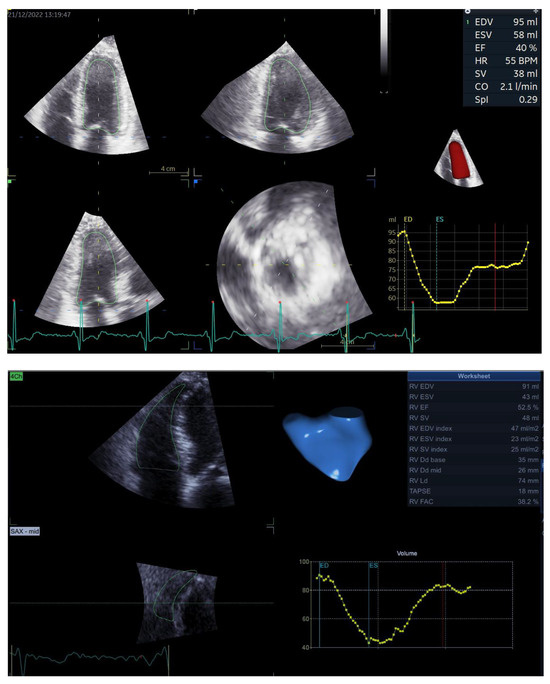

Based on the 3D atrial and ventricular volumes (Figure 1), we measured three atrioventricular coupling indices as follows: LACI, defined as the ratio between LA Vmin and LV EDV; RACI, defined as the ratio between RA Vmin and RV EDV; and CACI, defined as the sum between LACI and RACI. All the coupling indices were expressed as percentages, and a higher coupling index indicates a greater degree of atrioventricular decoupling.

Figure 1.

3D assessment using dedicated software for analysis of LV volumes and EF (upper panel), RV volumes and EF (middle panel) and atrial volumes (lower panel), upon which measurements of LACI, RACI and CACI are based. Abbreviations are in the text.